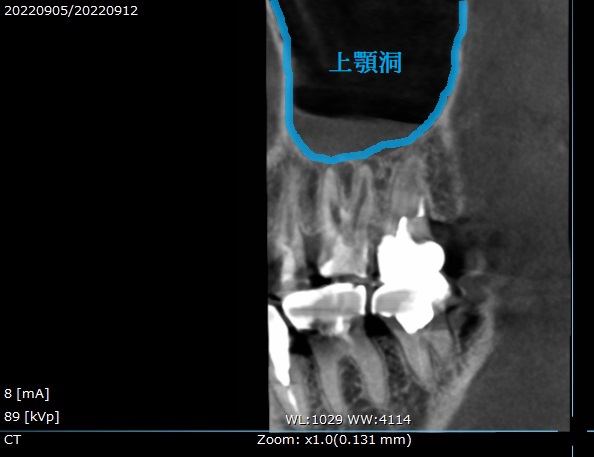

当院でCT撮影を行い状態を確認してみると、

☟このような状態でした。

青く囲まれている場所が「上顎洞」という、蓄膿症になる鼻の空洞です。

または「副鼻腔」とも言います。

そして

赤い所が歯の根っこ「根管」です。

今回治療する歯はこちらの上の6番目の歯。

一般の方はよく「奥から2番目の歯」とも言います。

つまりどうなっているかというと、

歯の中に細菌が入り込み、

歯の根の先で膿んでいます(青い所)

そしてその先の上顎洞に炎症が広がって、上顎洞内部が腫れています(赤い所)

これを歯性上顎洞炎(しせいじょうがくどうえん)と呼び、

歯が原因で上顎洞に炎症が起こっているという事です。

上の奥歯は、歯の根っこが上顎洞に近いために、

歯から細菌が入り、歯の空洞へ炎症が広がることが良くあります。